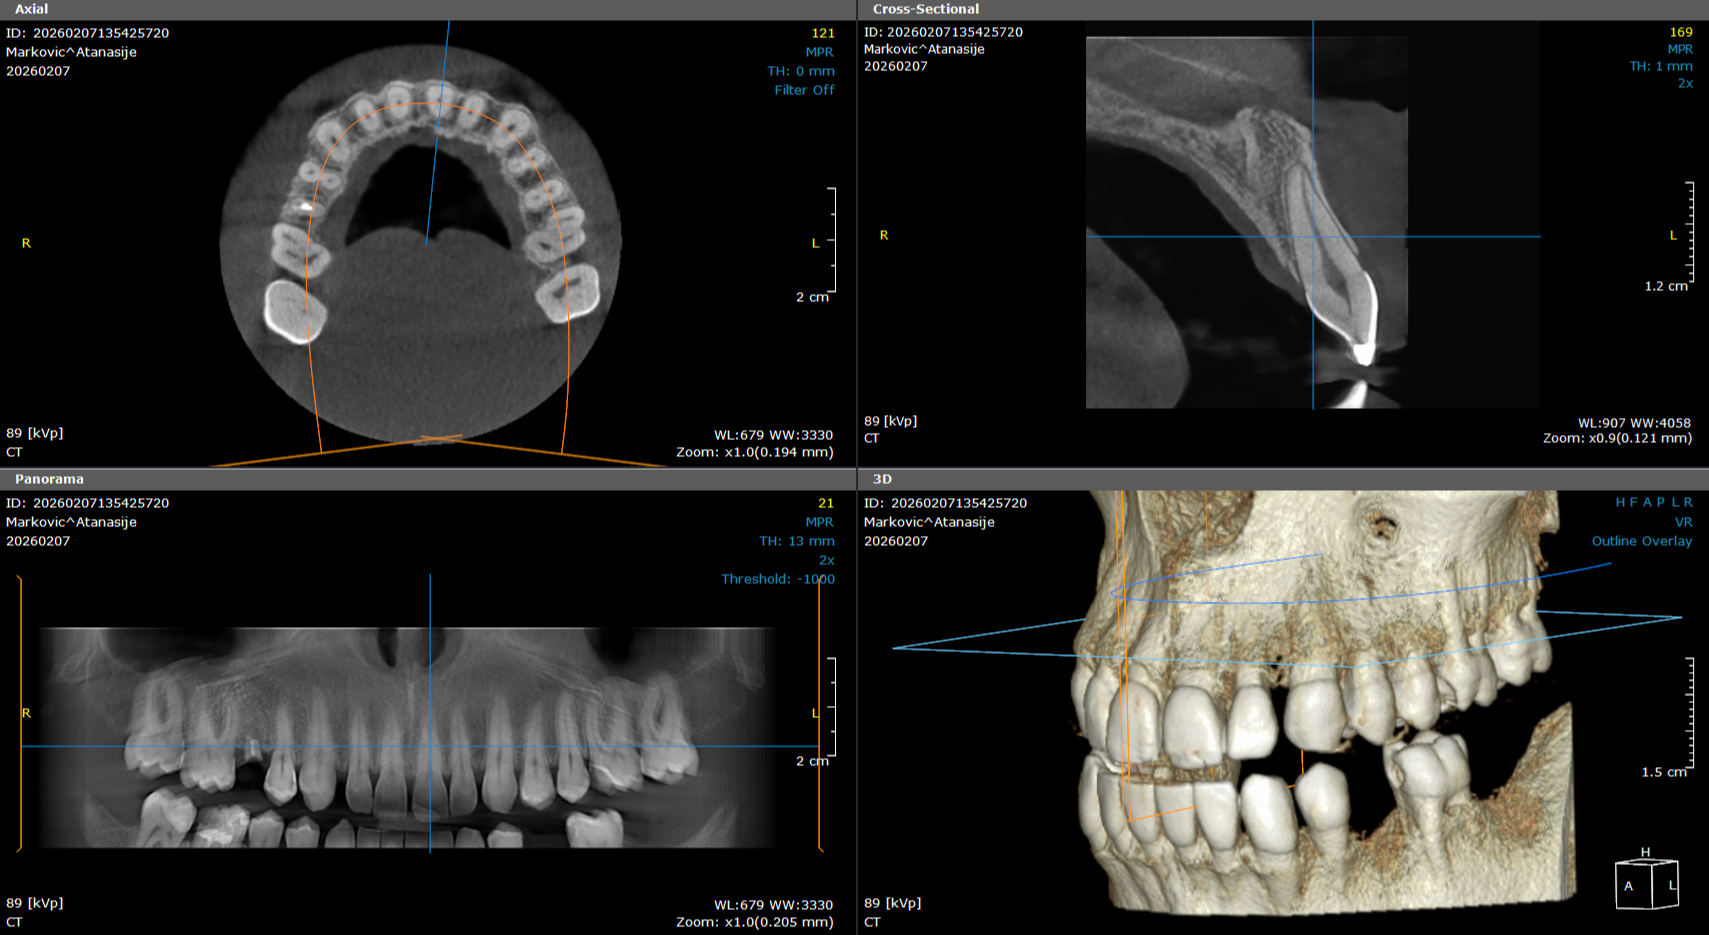

3D SNIMANJE ZUBA CBCT

3D snimanje zuba omogućava trodimenzionalni prikaz zuba i vilice. Ovaj snimak je posebno važan za planiranje implantata, oralnu hirurgiju i složene stomatološke terapije.